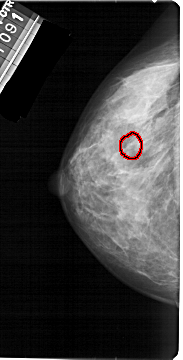

FILE: A_1392_1.LEFT_MLO.OVERLAY

TOTAL_ABNORMALITIES 1

ABNORMALITY 1

LESION_TYPE CALCIFICATION TYPE PLEOMORPHIC DISTRIBUTION CLUSTERED

ASSESSMENT 4

SUBTLETY 2

PATHOLOGY BENIGN

TOTAL_OUTLINES 1

BOUNDARY

LEFT_MLO LINES 5491 PIXELS_PER_LINE 2776 BITS_PER_PIXEL 12 RESOLUTION 43.5 OVERLAY